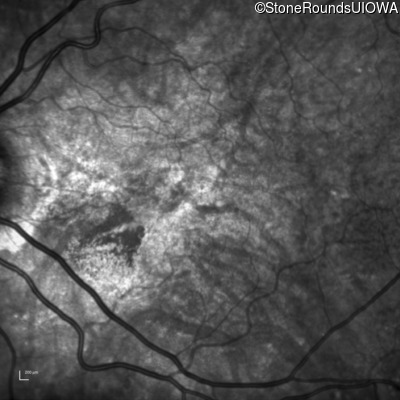

Age at visit: 58 years